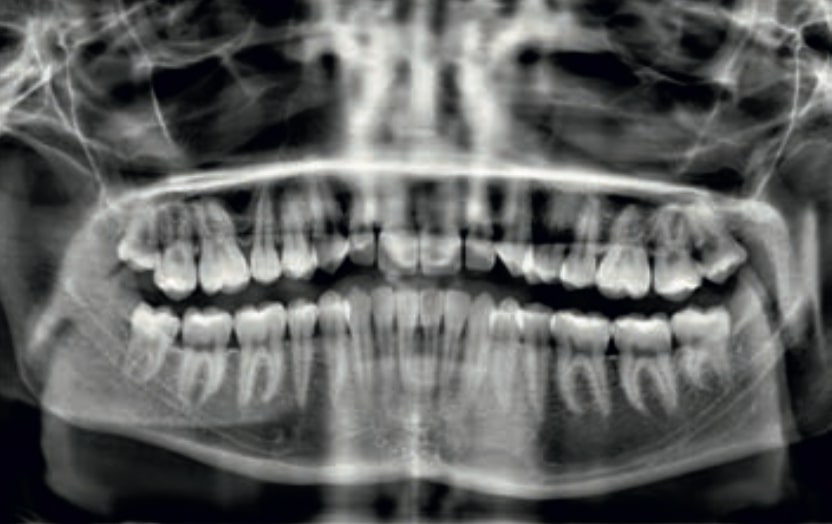

Chief complaint: The patient, a 19-year-old woman, was evaluated to undergo orthodontic treatment using the Angel Aligner Pro system. She presents with a skeletal Class III, mesofacial, with a dental Class III malocclusion and a 2 mm deviation of the lower midline to the left. Teeth 33 and 43 are out of the arch and cortical bone, with a crossbite issue on tooth 33. Fortunately, no functional issues affecting swallowing or breathing have been detected. The patient’s motivation for starting treatment was a general review of her dental and aesthetic health. The soft tissue analysis reveals mandibular protrusion that influences her facial profile. This diagnosis highlights the need for a comprehensive approach to address dental and skeletal misalignments, improving both the patient’s functionality and facial aesthetics.

Clinical examination and diagnosis

• Patient Age: 19 years old

• Skeletal class III

• Dental Class III, 2 mm deviation of the lower midline to the left. 33 and 43 out of the arch and the cortical bone.

• Crossbite of 33.

• No functional issues